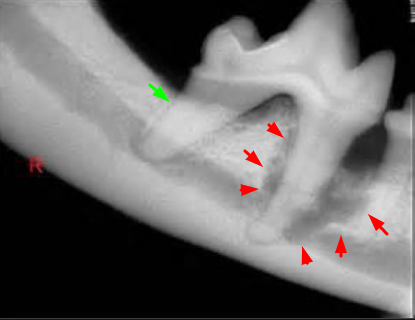

사진에 보이는것처럼 빨간색 화살표가 있는 부분처럼 치아가 박혀있는 뿌리 주변으로 감염이 일어나고

뼈가 녹아 헐렁해지면 치아가 흔들리고

그 후에 빠지는것이라

치아가 흔들거리고 있거나, 빠진적이 있다면 심한 치주질환을 몇년동안 앓다가 빠진겁니다.

이런 문제는 외견로 보는게 아니라 위의 사진처럼 치과 방사선 촬영을 통해 확인하는것이라